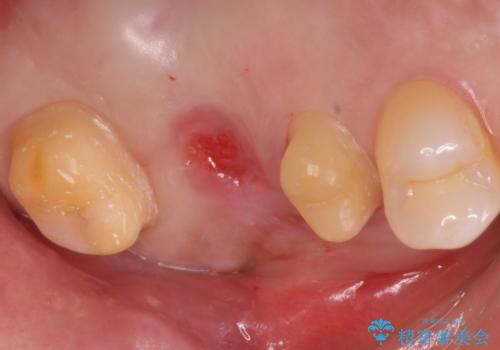

今回、残していた歯根から歯茎が大きく腫れ、長期的な予後を期待できないことを考慮し、抜歯してブリッジでの治療を行いました。

ブリッジでの修復は、抜歯後に歯がなくて噛みにくい期間が一切ありません。